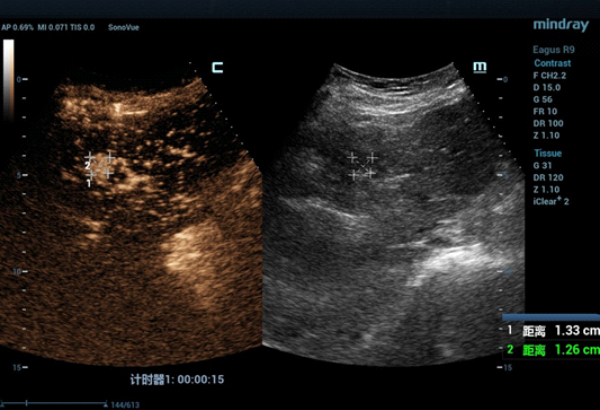

CT??? ??? S4?? ??? ??? ?? ???????? ??? ?????. CEUS(Contrast-Enhanced Ultra Sound)????? ?????? ??? ??? ??? ??? ???? ? ??? ???? ???? ??? ???????.

??? ????? ??? 2D ??? ??? ???? ???? ???? ??? ? ????? ??? ??? ?? ?????? ???? ?? ??? ???? ???? ??? ? ?????. ??? ??? ???? ??? ?? CT ??? ??? ???? ??? ??? ??? ?? MWA? ?? ???? ??? ???? ?????. CEUS(Contrast-Enhanced Ultra Sound)? ???? ?? ? ??? ??? ????, ?? ? ?? ??? ???? ?? ?? ??? ???????.?

?? ??? ??? CEUS(Contrast-Enhanced Ultra Sound)? ???? ????? ??? ??? ??? ???? ??? ? ??, ????? ???? ???? ????, ?? ??? ?????? ??? ? ????. ??? ??? ??? ???? ??? ?? ????? ??(Ultrasound-guided MWA)? ???? ?? ??? ?????.